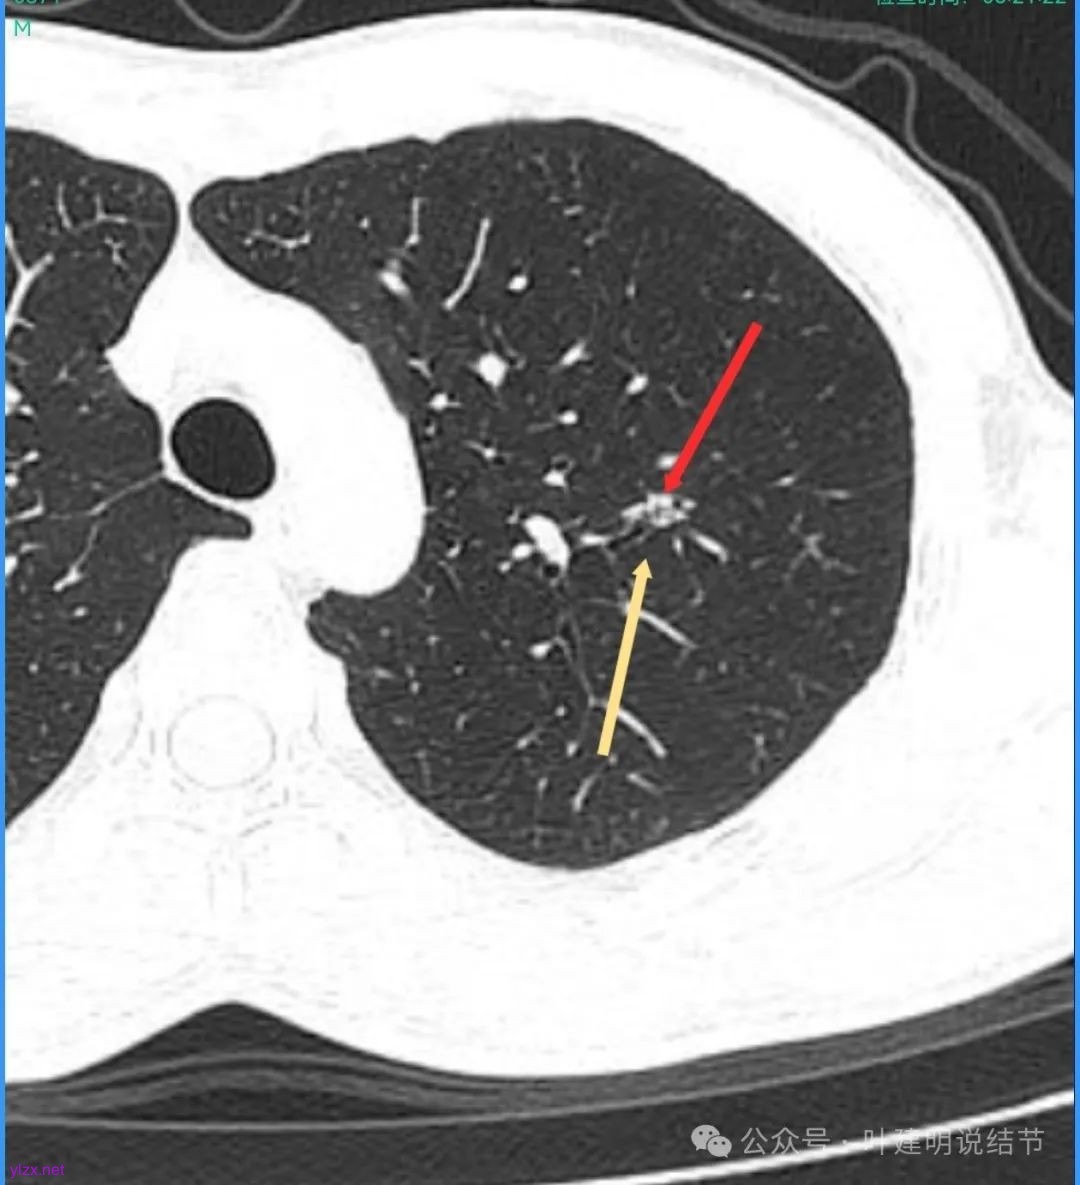

病灶密度不均,混合密度的样子,相应的细支气管有扭曲略显扩张。

边缘较为毛糙不平,灶内密度杂乱,细支气管穿行,整体轮廓较清。

邻近血管受结节影响,略向病灶侧弯,病灶处是扩张的细支气管还是灶内的空泡征?

有血管征,整体轮廓与边界较清,灶内有蜂窝状。

血管穿过病灶,灶内多个小空泡,整体轮廓较清。